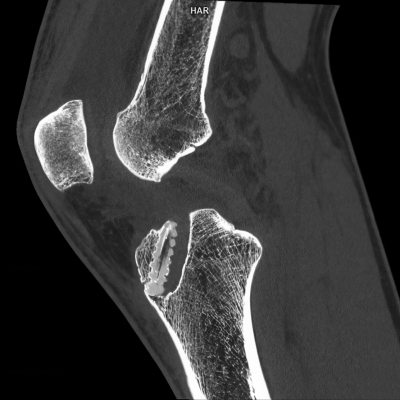

Handgelenk

Beim Gelenken sind mit dem Photon-Counting-CT Darstellungen von feinsten Strukturen möglich.